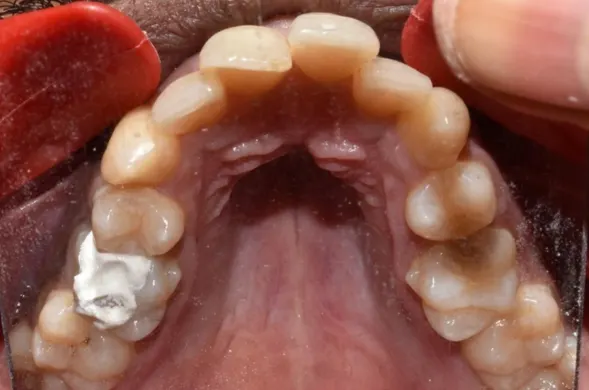

Before & After Results

At Aline Dent, we take pride in delivering visible and lasting improvements in our patients’ smiles. Our before-and-after results highlight the effectiveness of modern dental treatments combined with personalized care. This gallery showcases real dental cases treated at our clinic, giving you a clear idea of how different dental concerns can be corrected with the right treatment approach.

From minor corrections to complete smile enhancements, these teeth transformation results demonstrate how professional dental care can improve both oral health and appearance. Our experienced dental team carefully evaluates each patient’s needs and creates customized treatment plans to achieve natural, healthy, and confident smiles.

In this gallery, you will find a variety of smile makeover cases, including treatments for crooked teeth, gaps, discoloration, damaged teeth, and other common dental concerns.